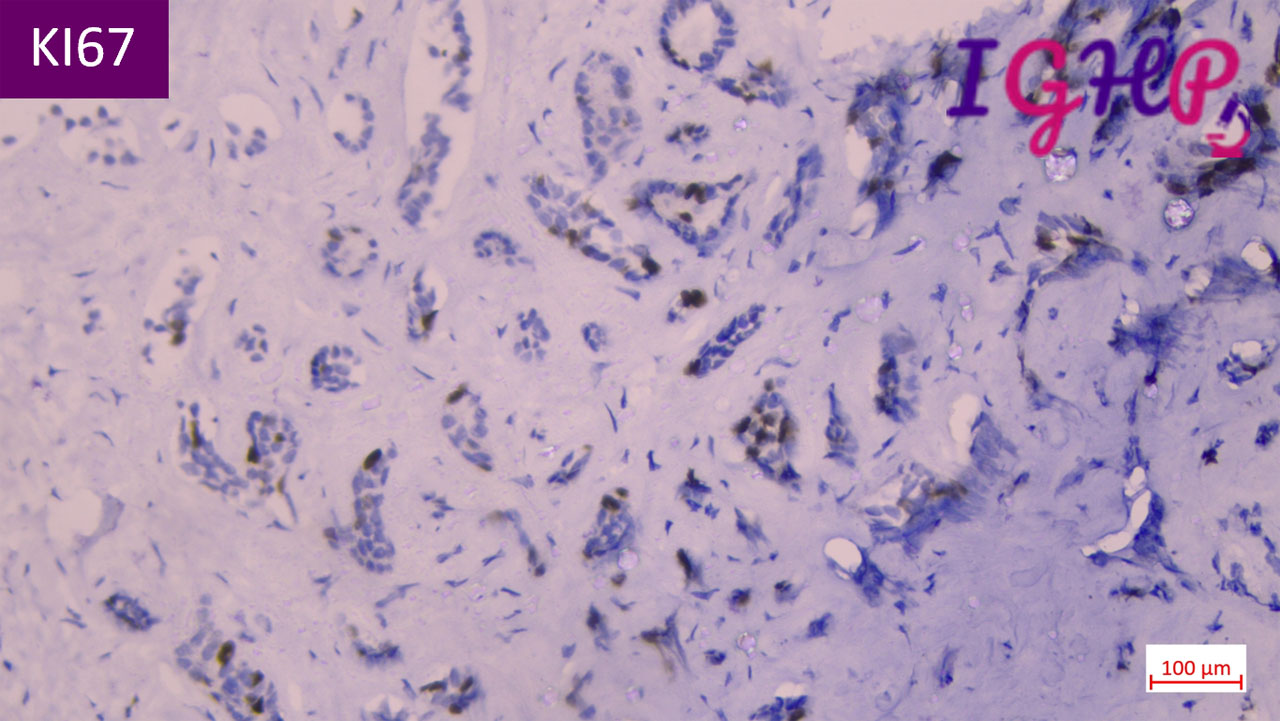

Immunohistochemistry Performed-

IHC performed for CK7, KI67 and P53